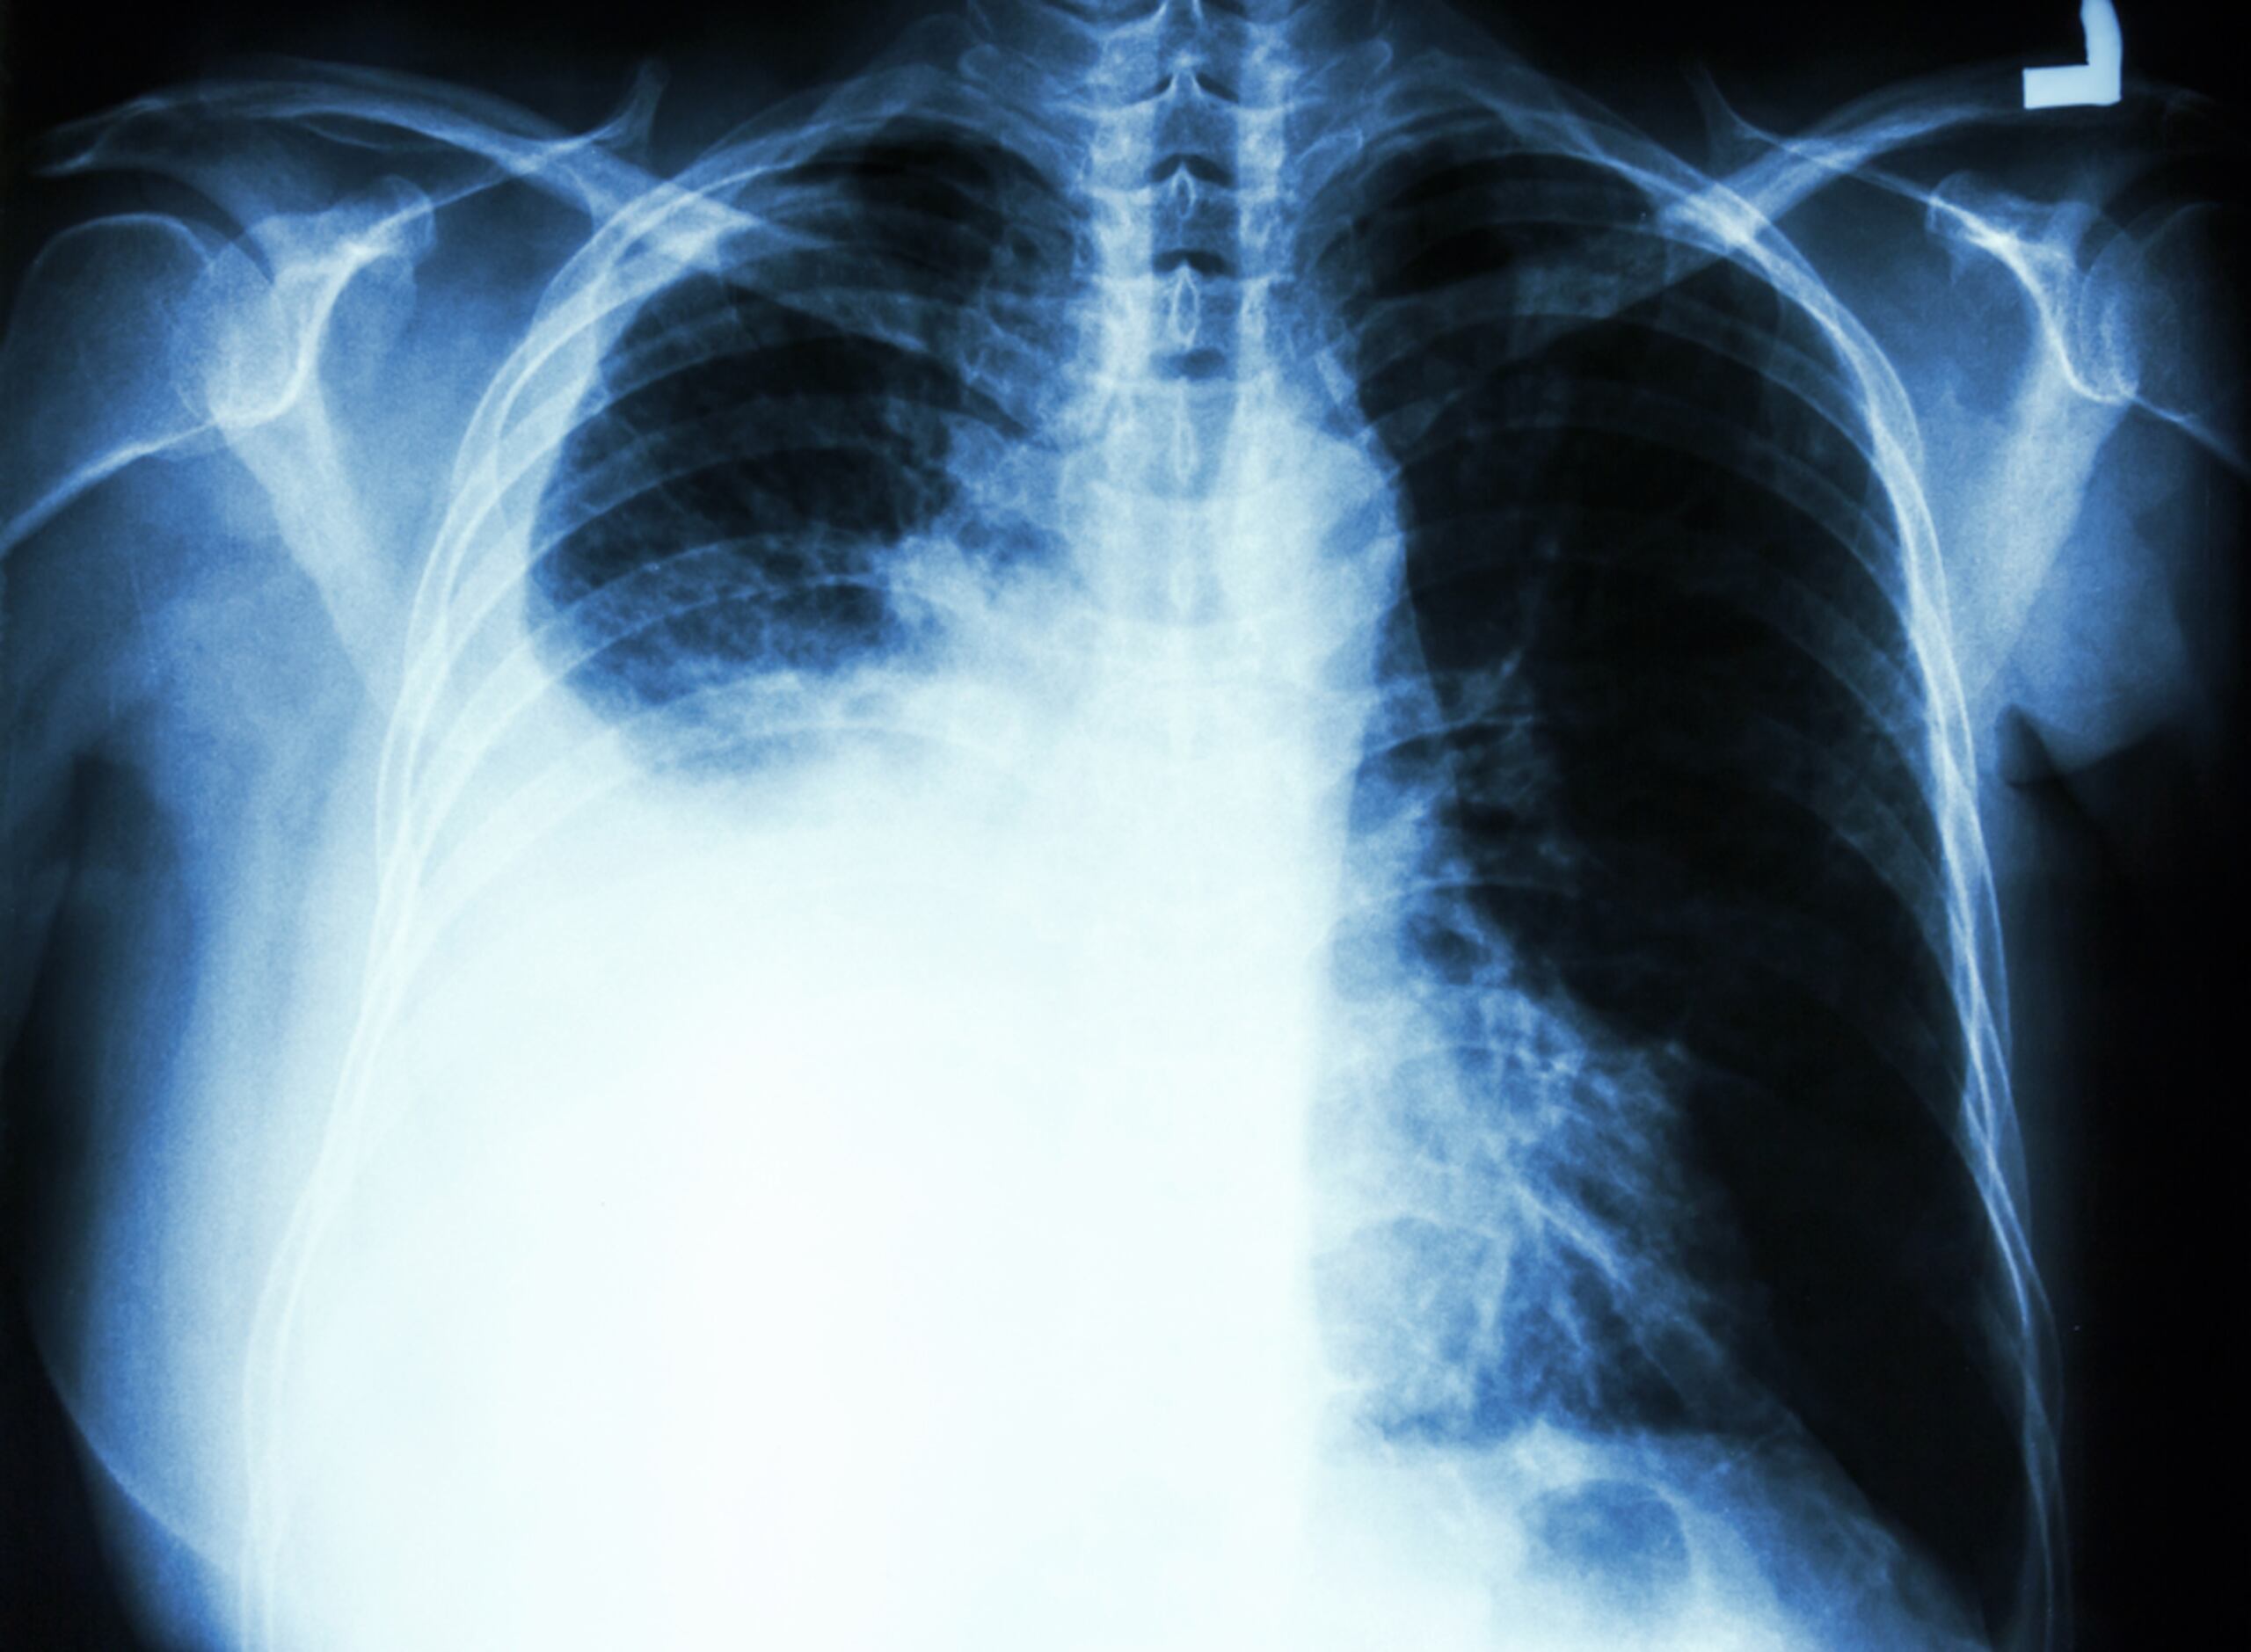

En Puerto Rico, el segundo cáncer más común en varones es el de pulmón y este es, también, el cáncer de mayor mortalidad. Tiende a ser bastante silencioso y está relacionado con el uso del cigarrillo.

“El paciente, cuando ha fumado por tanto tiempo y presenta lesiones de cáncer de pulmón relacionadas con el cigarrillo, coincide con diagnóstico de enfisema o COPD. Estos son pacientes más difíciles de tratar por las comorbilidades que tienen. Por eso, el cáncer de pulmón es la causa número uno de muerte por cáncer, tanto en hombres como en mujeres”, detalló la doctora Reyes.

“Las guías recomiendan que un paciente que llega a los 50 años y lleva más de 20 fumando, se haga un CT de baja intensidad (menos radiación) de cada 1 a 2 años. Lo que queremos es que, si encontramos lesiones tempranas, estos tumores puedan ser operados y tratados; no esperar a que esos pacientes, que llevan más de 40 años fumando, lleguen con una condición más avanzada”, indicó la hematóloga oncóloga, quien añadió que este cáncer es “altamente agresivo”.